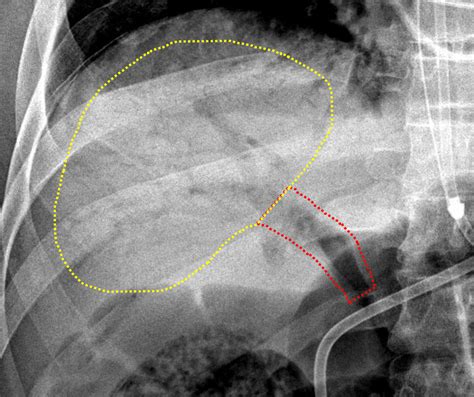

The gold standard for detecting portal venous gas is a CT scan of the abdomen, usually with intravenous contrast. On a scan, gas appears as low-attenuation, branching, linear lucencies that extend into the periphery of the liver. This pattern is distinct from pneumobilia (gas in the bile ducts), which typically resides in the central portion of the liver and follows the path of the biliary tree.

• portal venous gas on kub